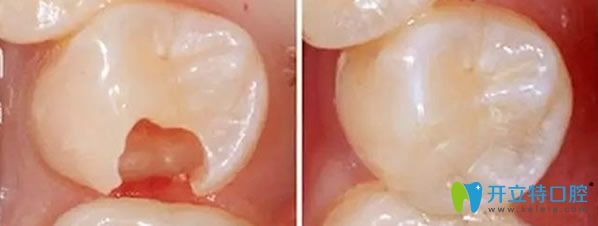

嵌體修復(fù)效果對(duì)比圖

嵌體的優(yōu)勢(shì),比傳統(tǒng)補(bǔ)牙要精細(xì),醫(yī)生在制作嵌體的時(shí)候,會(huì)控制它與牙體的彌合程度,盡可能的避免了牙齒在日后的使用中再次出現(xiàn)齲壞??梢曰謴?fù)原來(lái)牙齒的外形,增加牙齒的咀嚼功能。